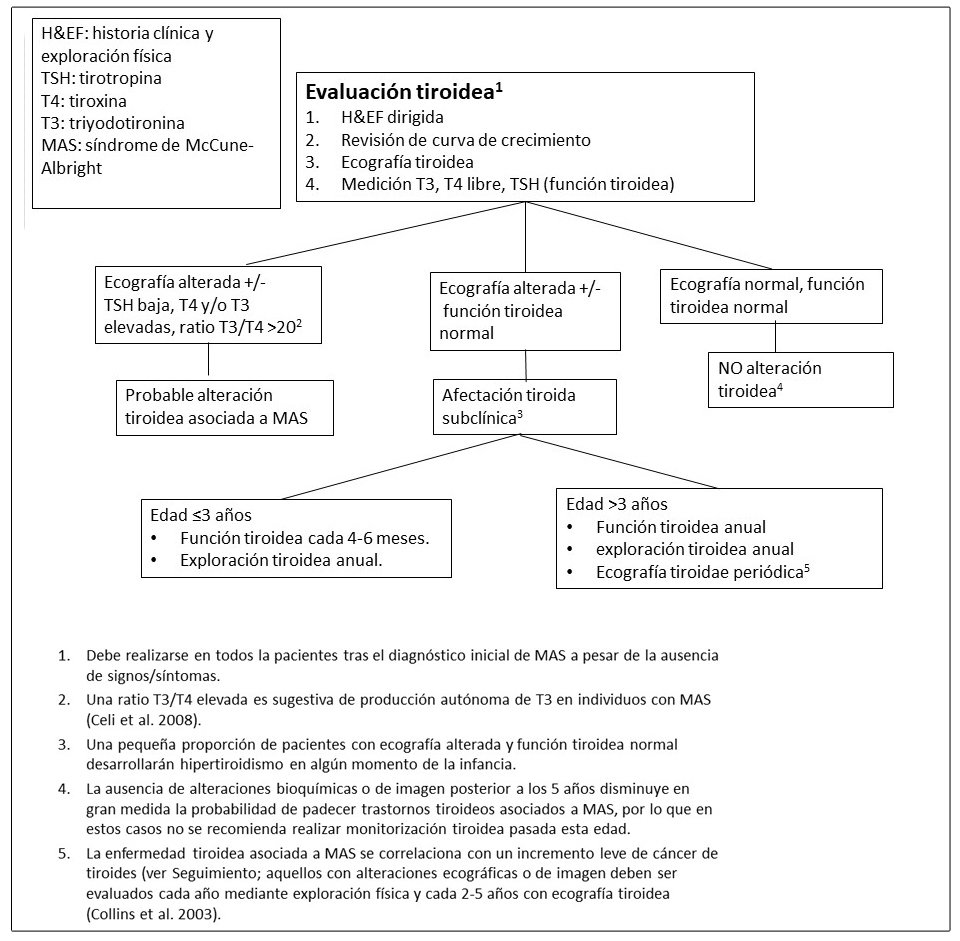

Figura 8. Pruebas y seguimiento recomendado para la evaluación de alteraciones tiroideas en pacientes con Displasia Fibrosa/Síndrome de McCune-Albright

Enfermedad tiroidea.

La afectación de la glándula tiroides es muy frecuente en los pacientes con DF/MAS. Se detectan alteraciones ecográficas tiroideas en aproximadamente la mitad de los individuos con DF/MAS. Estas alteraciones incluyen la presencia de lesiones mixtas solido-quísticas y lesiones sólidas entremezcladas con áreas de tejido de apariencia normal. (Figura 4C y 4D) (Celi et al 2008, Tessaris et al 2012a).

El hipertiroidismo suele afectar al 10-30% de los individuos con DF/MAS y es el resultado de tanto el incremento de producción hormonal como del incremento de la conversión de tiroxina (T4) a triyodotironina (T3) (Celi et al 2008). El hipertiroidismo suele ser leve o moderado, pero en ocasiones puede ser más grave pudiendo incluso llegar a provocar una tormenta tiroidea durante la inducción anestésica prequirúrgica (Lawless et al 1992).

El hipertiroidismo no tratado puede resultar en el adelanto de la edad ósea, en la elevación del remodelado óseo y en fracturas.

La transformación maligna de los tejidos tiroideos afectos puede ocurrir de manera excepcional (Collins et al 2003).